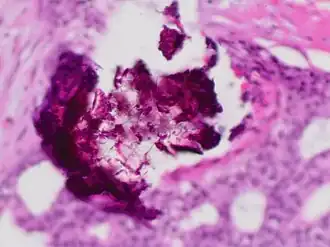

Histopathology of dystrophic calcium phosphate microcalcifications in ductal carcinoma in situ (DCIS) of the breast, H&E stain.

Histopathology of dystrophic calcium phosphate microcalcifications in ductal carcinoma in situ (DCIS) of the breast, H&E stain. -

In contrast to an artifact of crowded cells, the DCIS calcification pictured above characteristically extends outside the focal plane, as the background DCIS is blurred in this focus.